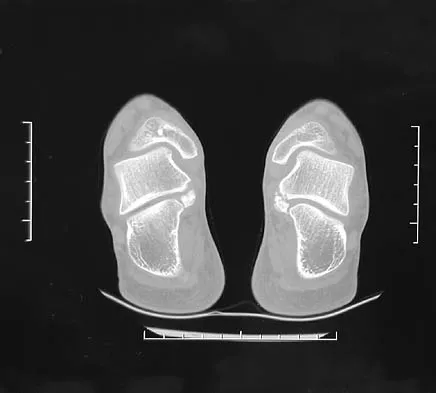

Figure 8 shows the CT scan of an 11-year-old boy who has had a 1-year history of worsening painful flatfeet. He reports pain associated with physical education at school, especially with running and jumping. Management consisting of activity restriction, anti-inflammatory drugs, and casting has failed to provide relief. Treatment should now consist of